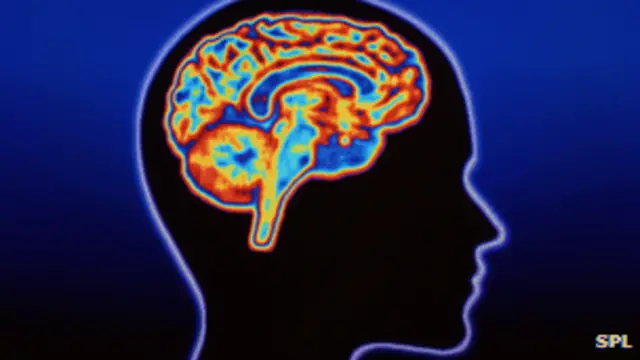

Para ellos es más importante no vivir a la sombra de la enfermedad, que afecta las células en el cerebro, impidiendo que el cuerpo y el cerebro funcionen tan bien como antes.

Afecta los movimientos, el pensamiento y el comportamiento y, en la mayoría de los casos, el paciente comienza a sufrir un deterioro lento, a lo largo de 15 o 20 años.